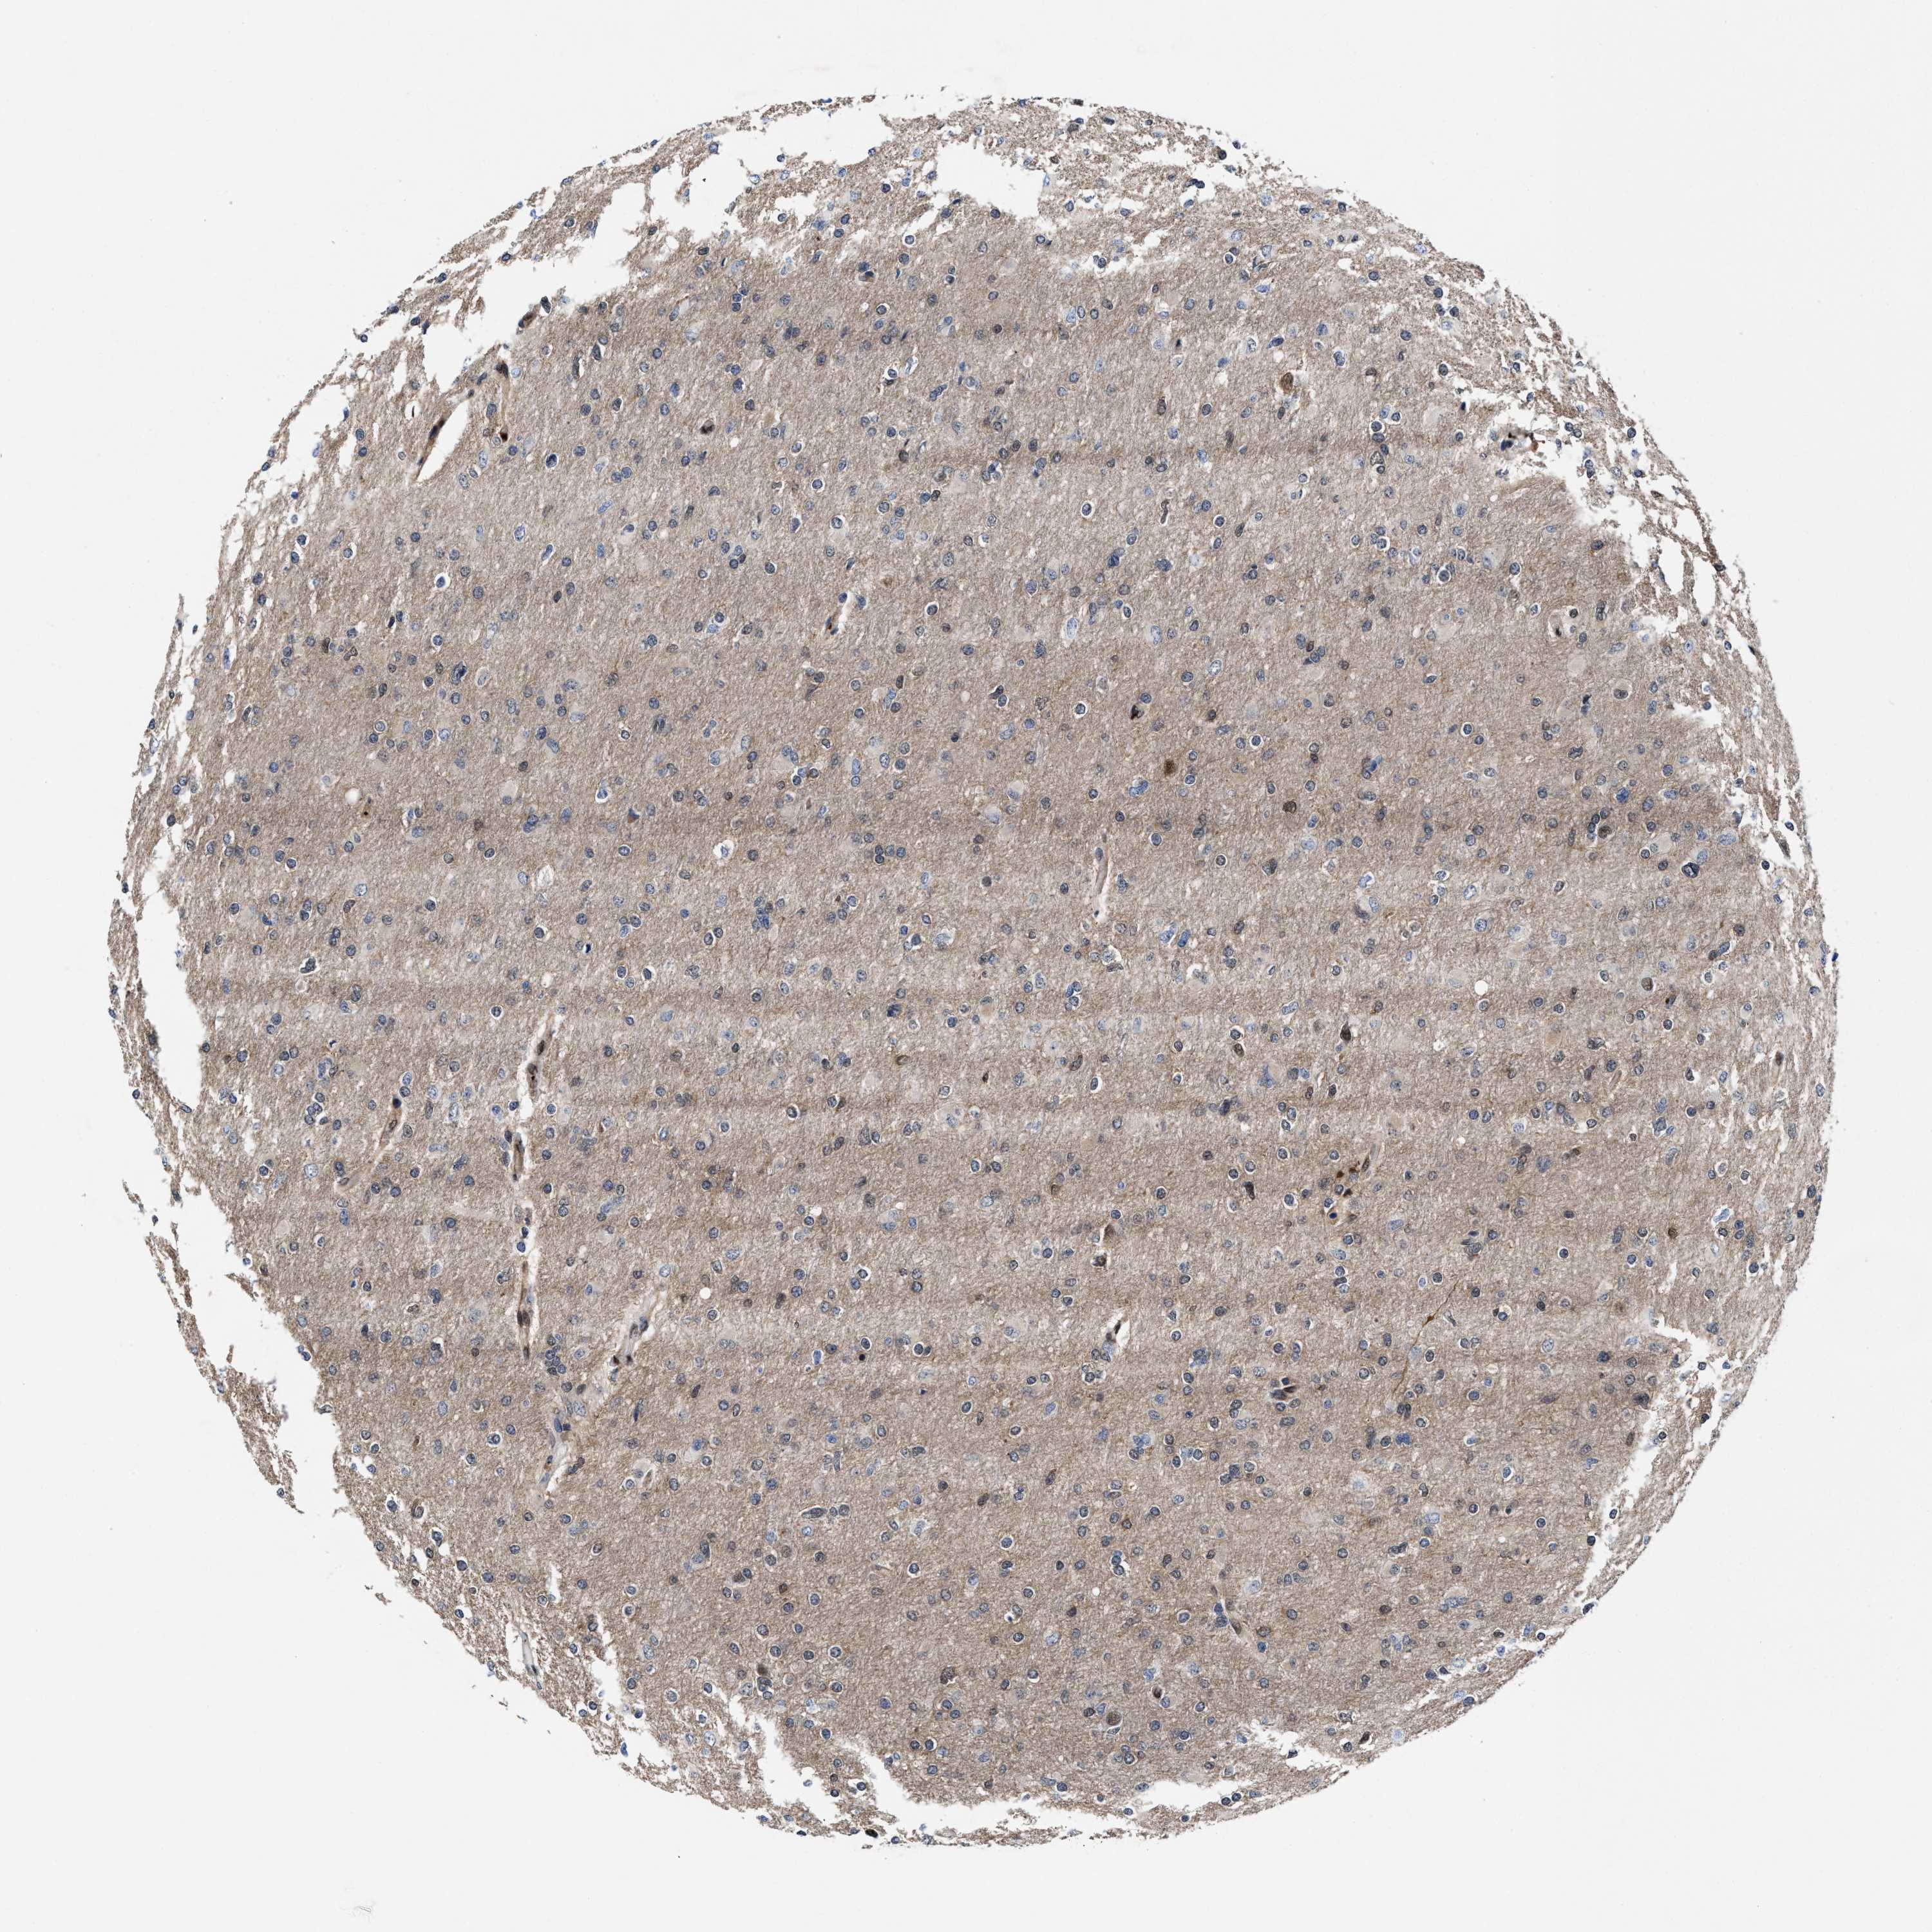

GLIOMA - Protein expressioni

A mouse-over function shows sample information and annotation data. Click on an image to view it in a full screen mode. Samples can be filtered based on level of antibody staining by selecting one or several of the following categories: high, medium, low and not detected. The assay and annotation is described here.

Note that samples used for immunohistochemistry by the Human Protein Atlas do not correspond to samples in the TCGA dataset.

Antibody stainingi

Antibody staining in the annotated cell types in the current human tissue is reported as not detected, low, medium, or high, based on conventional immunohistochemistry profiling in selected tissues. This score is based on the combination of the staining intensity and fraction of stained cells.

Each image is clickable and will lead to virtual microscopy that enables deeper exploration of all samples and also displays staining intensity scores, fraction scores and subcellular localization as well as patient and tissue information for each sample.

HPA022434

HPA022953

HPA022959

HPA028758

CAB007783

Glioma, malignant, High grade

Glioma, malignant, Low grade

Glioblastoma, NOS